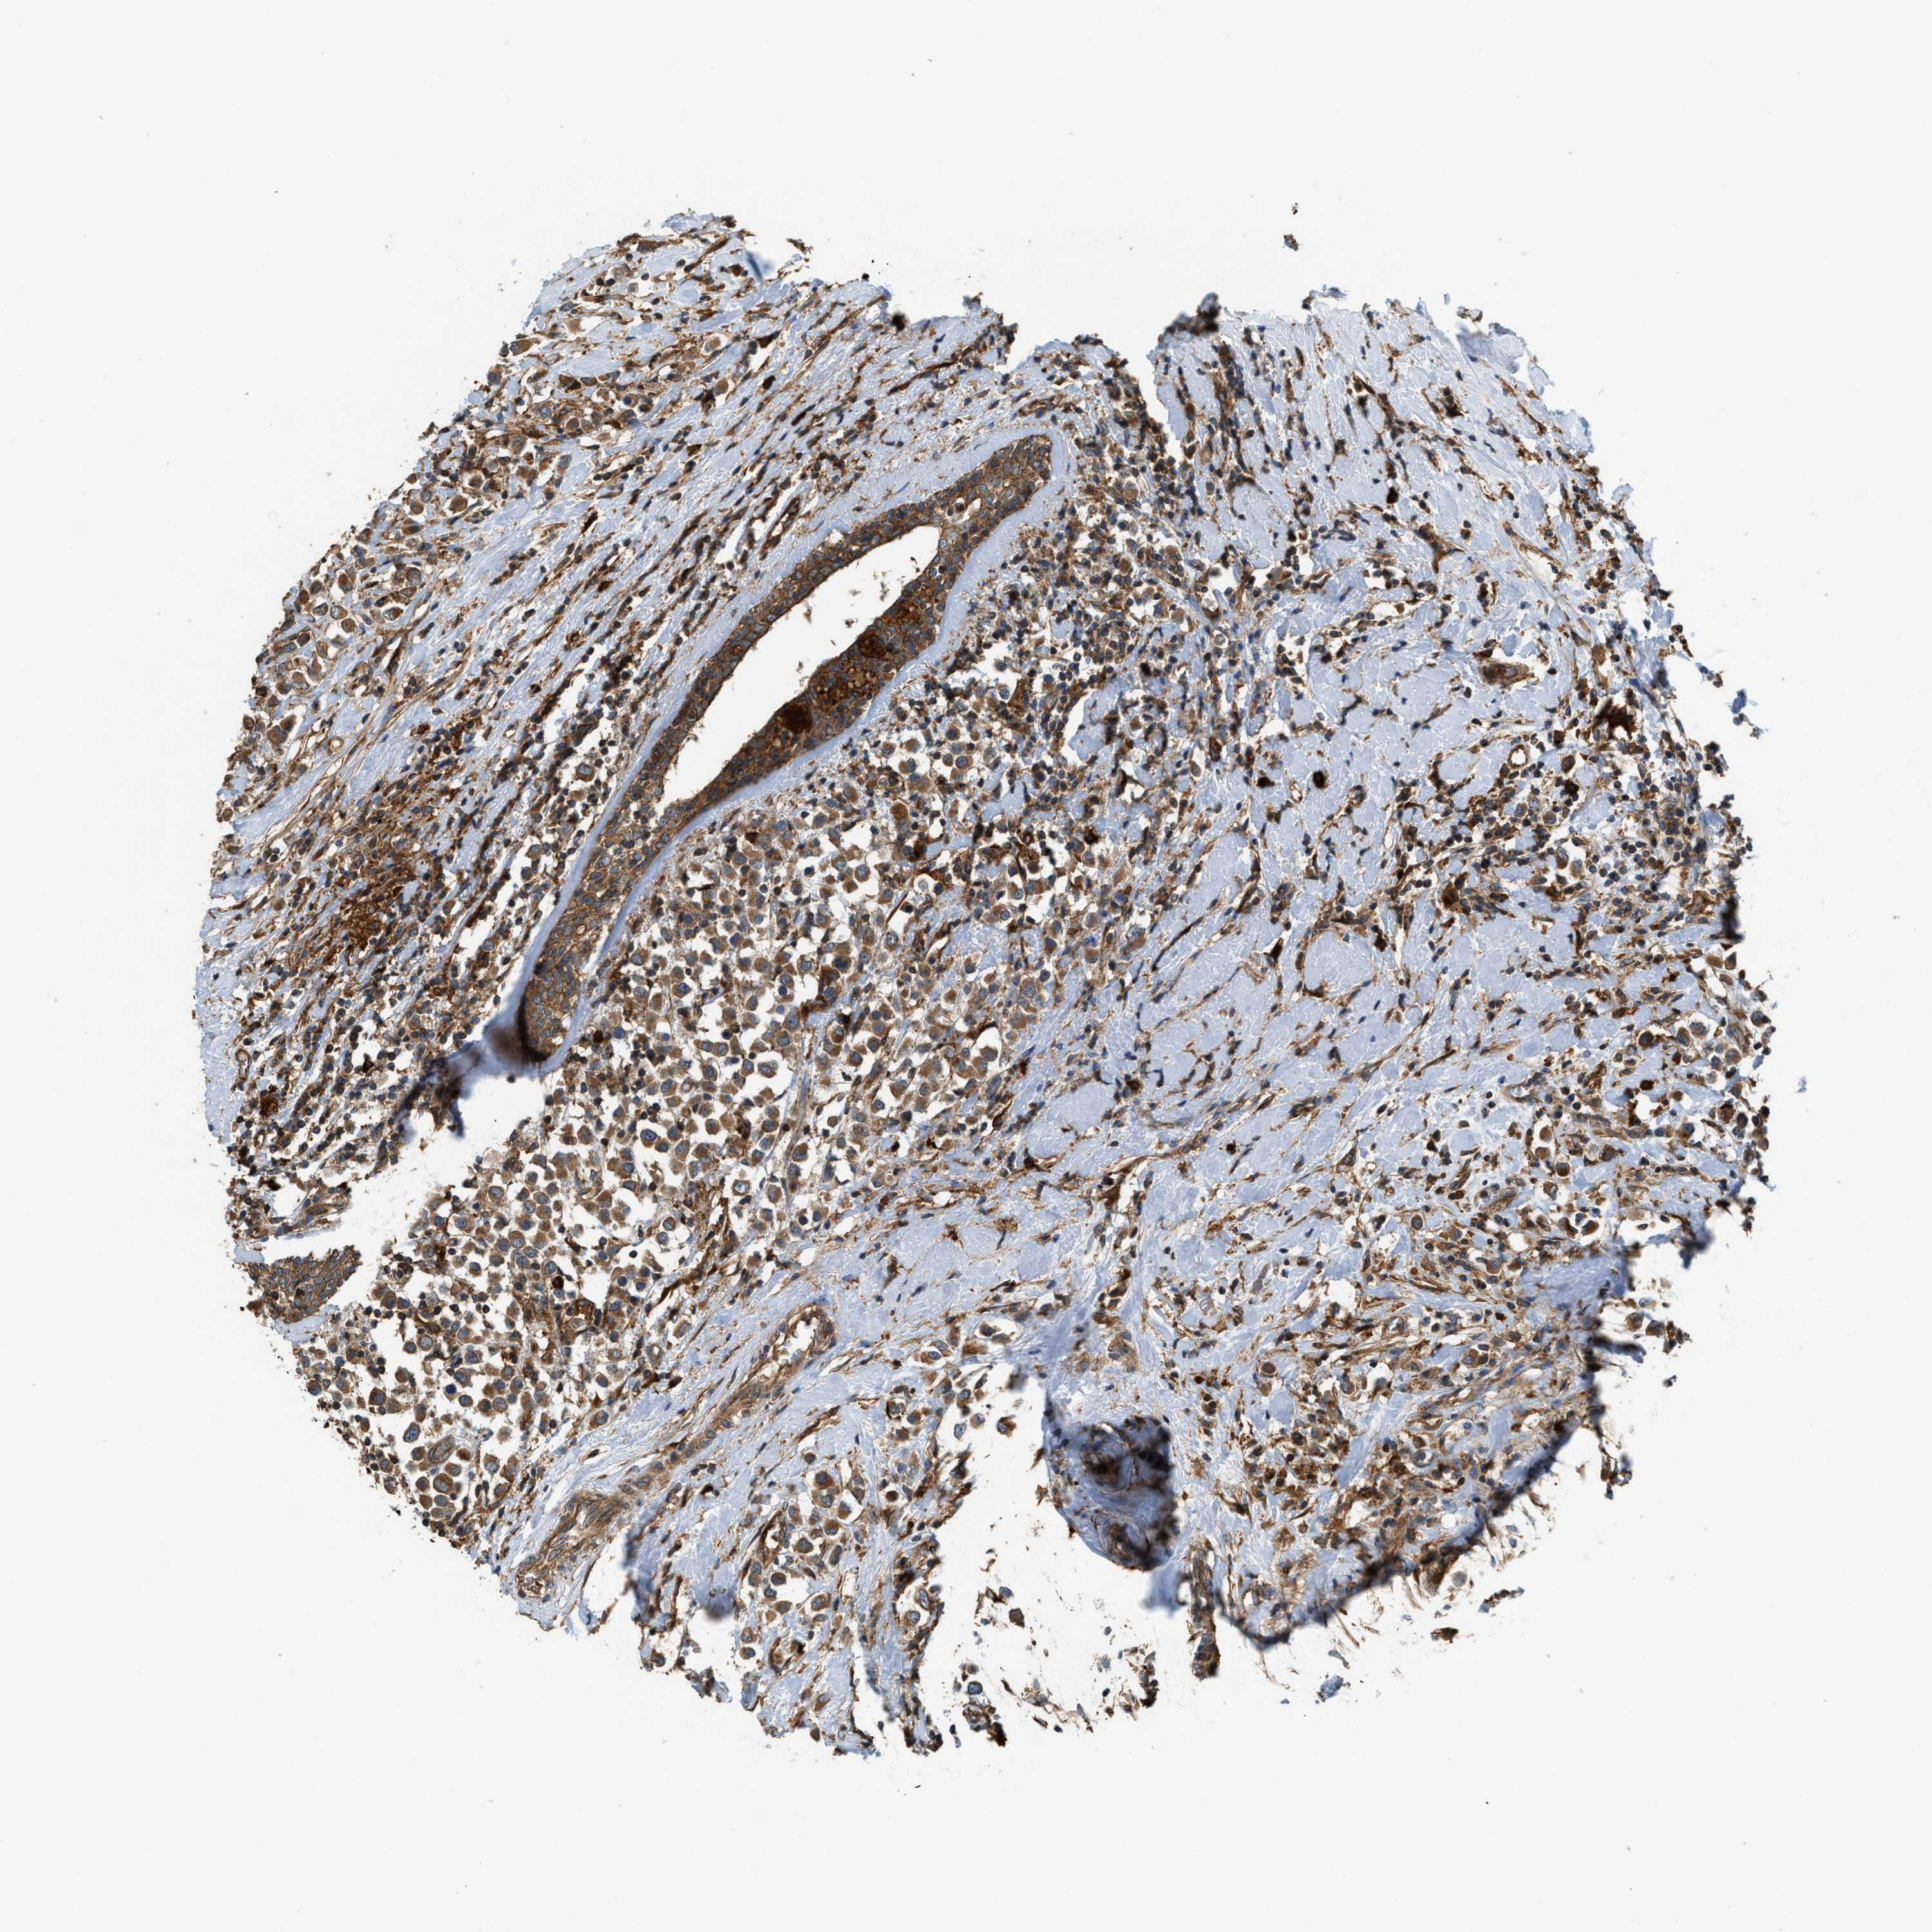

CANCER BREAST CANCER Show tissue menu

BRCA TCGA BRCA VALIDATION PROTEIN EXPRESSION

ANTIBODIES

AND

VALIDATION